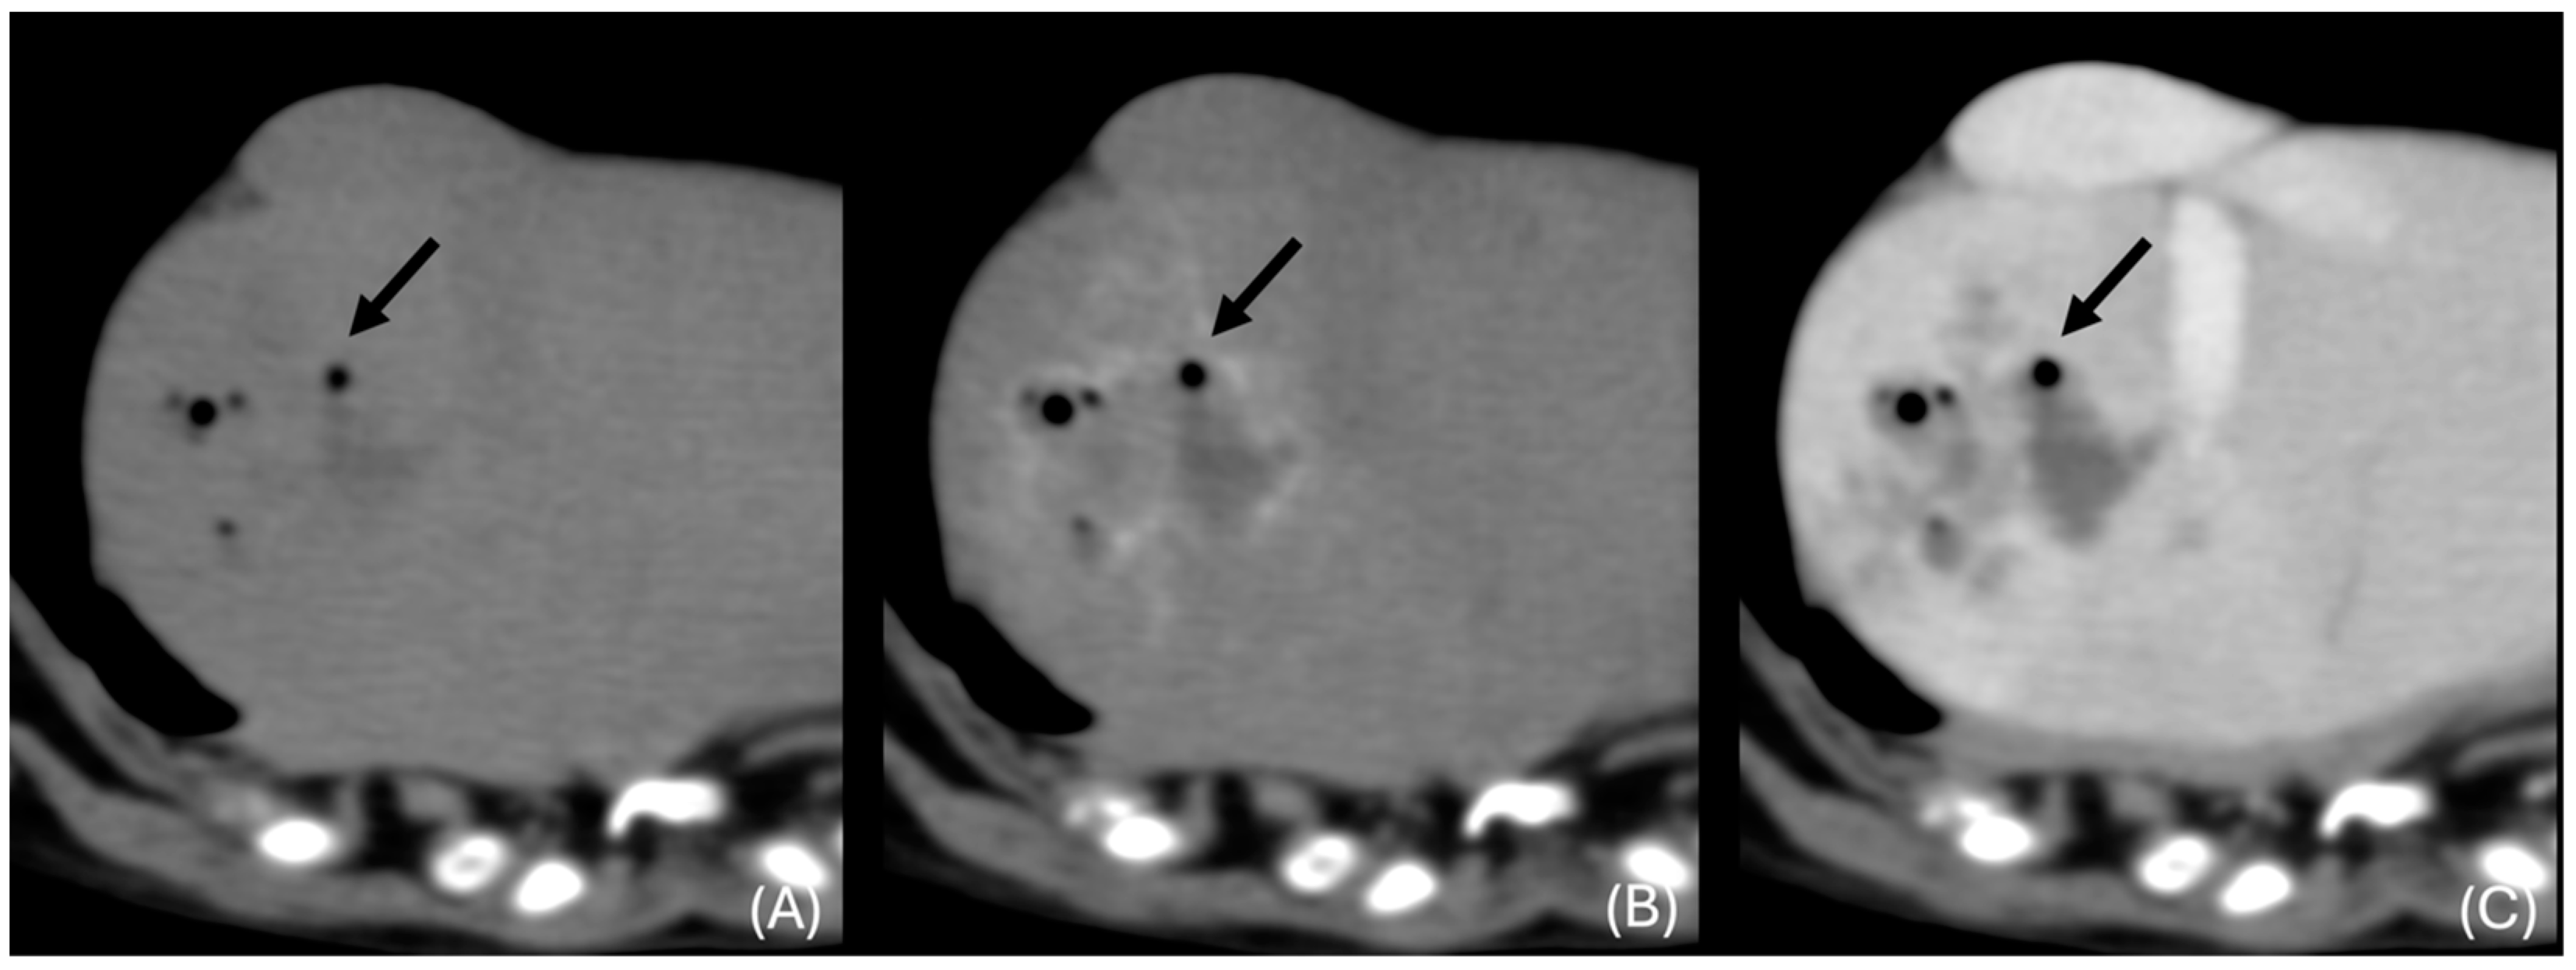

3.6.2. “Discrete” Changes